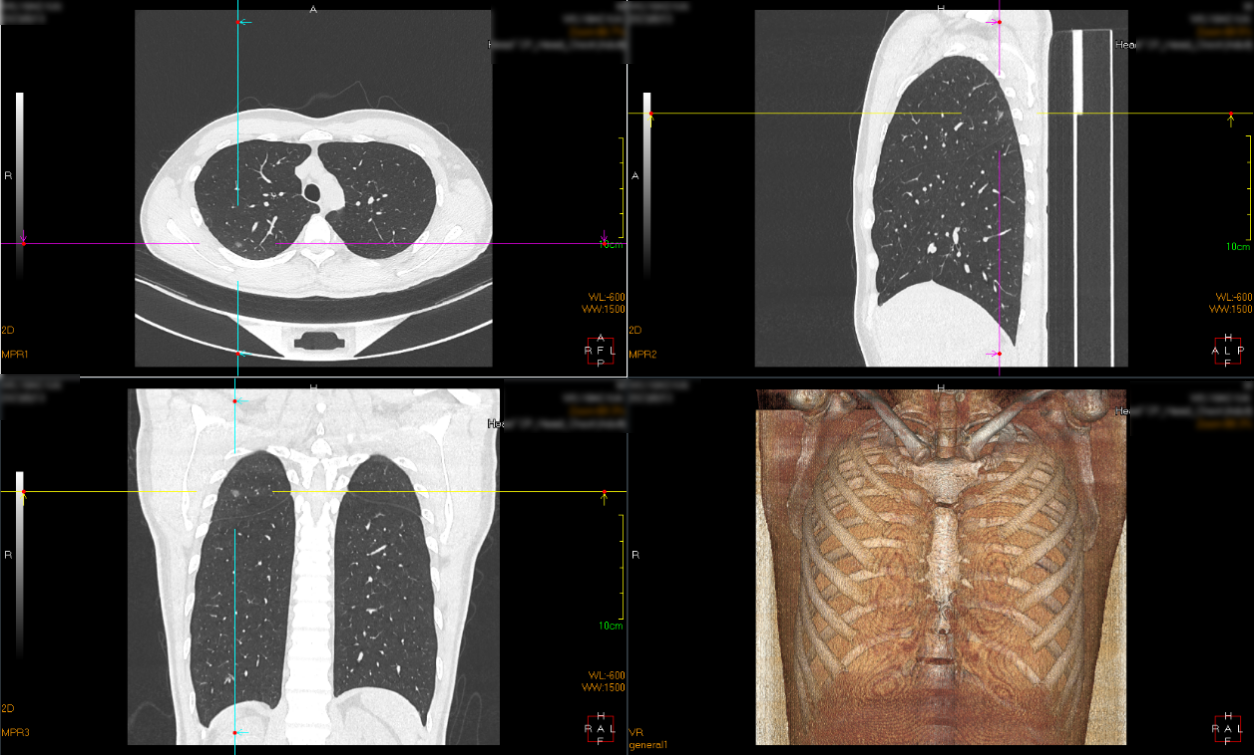

术前胸部CT